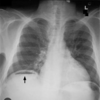

Peritonitis can cause pneumoperitoneum. What imaging modality is best to detect the presence of pneumoperitoneum? 1 - erect chest X-ray 2 - supine chest X-ray 3 - erect MRI scan 4 - erect CT scan

1 - erect chest X-ray - air will rise to the above the liver